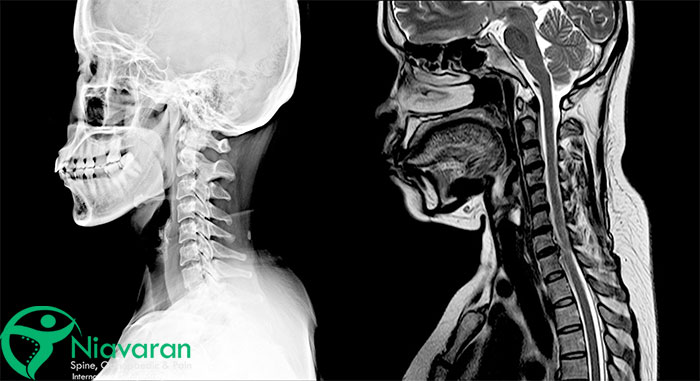

mr گردن برای چیست؟ ام آر آی گردن (Cervical Spine MRI Scan) یک روش تصویربرداری غیرتهاجمی است که برخلاف اشعه ایکس یا سیتیاسکن، از میدان مغناطیسی قوی و امواج رادیویی برای ایجاد تصاویر دقیق از استخوانهای ستون فقرات گردنی، بافتهای نرم و اعصاب اطراف گردن شما بدون خطر قرارگرفتن در معرض تشعشع استفاده میکند. این تصاویر با جزئیات بالا میتوانند به پزشکان در تشخیص و ارزیابی طیف گستردهای از بیماریها و آسیبهای مرتبط با گردن مانند آرتروز گردن، برآمدگی دیسک، فتق دیسک، تومور، آنوریسم و برخی اختلالات خودایمنی کمک کنند.

- ارائه تصاویری بسیار دقیق از ستون فقرات گردنی شما برای تشخیص جزئیات کوچکی که ممکن است با سایر روشهای تصویربرداری قابلمشاهده نباشد

- عملکرد بهتر در تصویربرداری از بافتهای نرم؛ مانند عضلات، رباطها، تاندونها، دیسکها و مایع مغزی نخاعی و تشخیص آسیبها یا التهاب در این بافتها

- ارائه اطلاعات و تصاویر چندبعدی از ستون فقرات گردنی شما برای درک بهتر آناتومی و عملکرد آن توسط پزشکان و نهایتاً تشخیص و درمان دقیقتر

تفسیر جواب ام آر ای گردن میتواند یک فرایند پیچیده باشد که به تخصص و تجربه پزشکی قابلتوجهی نیاز دارد. برای درک صحیح تصاویر ام آر آی، ضروری است که پزشک از آناتومی پیچیده ستون فقرات گردنی و ساختارهای اطراف آن آگاهی کامل داشته باشد. معمولاً طول میکشد تا یک پزشک واجد شرایط، مانند رادیولوژیست، دکتر دیسک گردن یا متخصص مغز و اعصاب، نتایج ام آر آی گردن شما را تفسیر کند.

در طول تفسیر و خواندن mri گردن، آنها به دنبال ناهنجاریهایی مانند فتق دیسک، تنگی کانال نخاعی، آرتروز، تومور یا آسیب به استخوانها، عضلات یا رباطهای گردن شما خواهند بود. تفسیر MRI گردن باید در کنار سایر یافتههای بالینی، مانند سابقه پزشکی، معاینه فیزیکی و نتایج سایر آزمایشات، انجام شود تا تصویر کاملی از وضعیت بیمار ارائه شود.